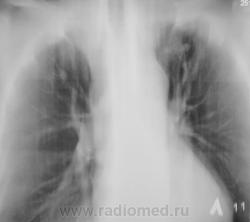

туберкулёз. Имеется небольшое расширение тени средостения в верхнем этаже.

Возможно туберкулома, но надо дифференцировать с периферическим раком лёгкого. ИМХО: средостение, вероятно не изменено, просто так вышло в положении лёжа ( стоя по обзорному снимку, тень средостения не изменена).

Валентин Львович, по-моему, это все-таки так любимые Вами "красавицы".

Периферический рак вряд ли, там же не одна тень. Без твс не обошлось.

Возраст 55 лет. Жалоб нет.

не исключить  метастазы

Пациентку забрали фтизиатры.